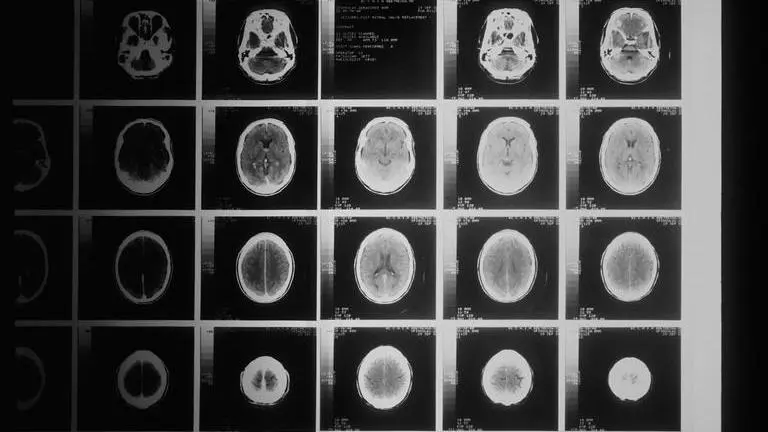

In a mysterious story, a man from New Jersey named Al Lupiano found out that 100 people with uncommon cancers were linked to Woodbridge Township School District, Colonia High School. Lupiano was diagnosed with a rare and abnormally large brain tumour Acoustic Neuroma (AN) in 1999 when he was just 27 years old.

As per the reports of Fox, his wife and now-deceased sister were both diagnosed with uncommon forms of brain cancer. He revealed in a Facebook post that his wife was diagnosed with an abnormally large AN tumour and that his sister was diagnosed with Glioblastoma Multiforme (GBM), which has an occurrence rate of 30 per million people.

Lupiano remembered that he, his wife and his sister all attended Colonia High School in Woodbridge in the 1990s, but he was not convinced that the high school was linked to uncommon brain cancer cases until he asked others who attended Colonia to contact him directly on Facebook. He stated that more than 100 former Colonia High School students had been diagnosed with uncommon cancers as of April 11.